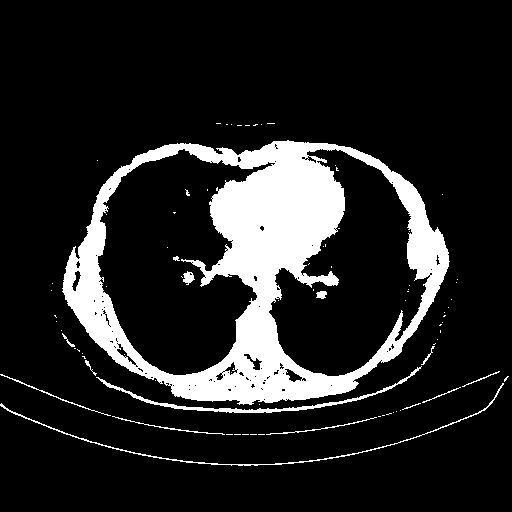

Slice 70 Targeting Evaluation

Patient ID: BM26032018

Model: cytran

Slice: Slice_70

Slice Thickness: 2.0mm

Conversion: NATIVE β VENOUS

| BM26032018_slice_70 | 0.851 | 120.735 | 53.448 | 0.896 | 44.2 | 19.6 | 0.893 | 11.8 | 5.2 |

4Γ3 grid: Rows show different image types (Original NATIVE, Reconstructed NATIVE, Original VENOUS, Generated VENOUS), Columns show windowing techniques (No Window, Lung Window, Mediastinum Window)